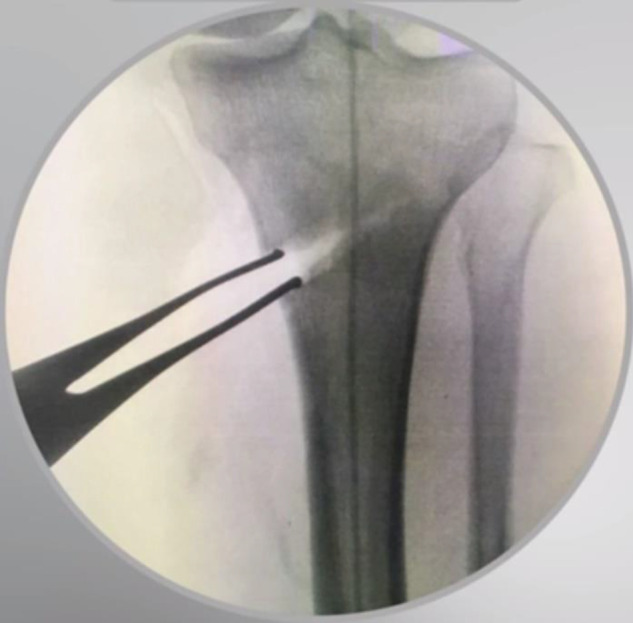

Medial open-wedge high tibial osteotomy (MOWHTO) is increasingly recognized as the preferred treatment option for active patients with varus malalignment and medial compartment osteoarthritis of the knee. This procedure aims to delay the degenerative process while alleviating pain and dysfunction. In this technical note, we aim to describe the tips and tricks for performing a safe MOWHTO, drawing on recent literature.